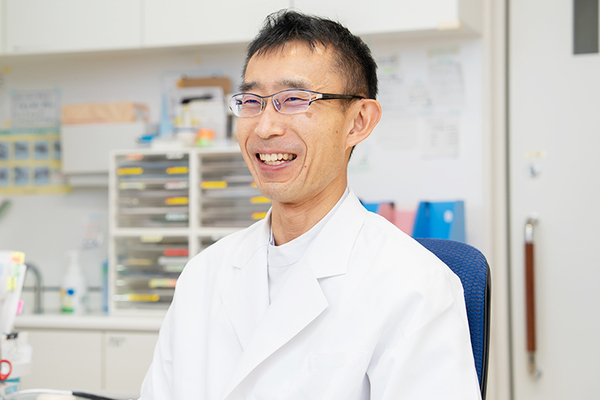

迅速で精密な診断は、適切な治療への第一歩。必要と考えられる検査機器はできる限り取りそろえています。血糖値やヘモグロビンA1c値や甲状腺ホルモン値、脂質、尿酸、電解質、血算、炎症を示すCRP値など、当日の診断に必要な項目を院内で測定できるよう設備を整えています。胸部レントゲンの画像診断では、全例でAI技術による画像診断支援システムを使用しています。AIの解析でダブルチェックを行うことで、見逃しの防止や、診断の精度向上につなげています。もちろん、設備だけでなく「人」の力も重要。最近、心臓の超音波検査ができる臨床検査技師が新たに加わり、甲状腺や腹部、頸動脈に加え、心臓まで含めた幅広い超音波検査が可能になりました。医師だけでなく、看護師や管理栄養士といったスタッフがそれぞれの専門性を生かし、患者さんの健康を支えています。